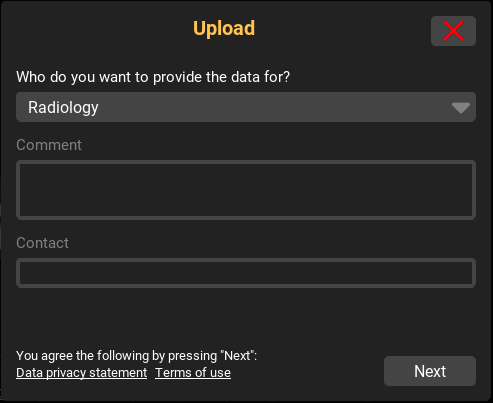

9.1.1. DICOM Upload

If the upload has been activated on the server side, you can upload DICOM data to the server using the "+" button or drag’n’drop (dragging files into the inbox). When using the "+" button, a dialog for selecting the upload data will appear beforehand. If several upload destinations (e.g. departments) are available for you, another dialog will appear. You can use this dialog to select the upload target and, if required, to enter further details about your upload. After confirming all details, the files will be uploaded to the server. As soon as the data has been successfully uploaded and imported on the server side, it will appear in your inbox for the image display. Furthermore, there is an upload report in each uploaded study. This summarizes and logs all upload information (uploader, date, number of files, manual entries, etc.) once again.